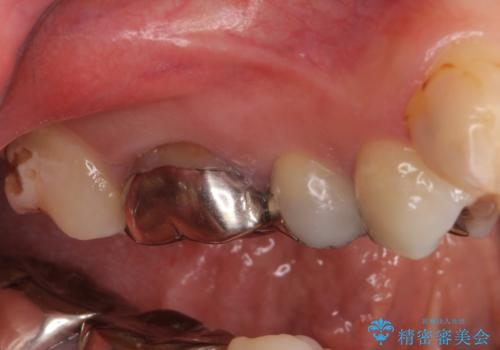

- 笑ったときに見てしまう上顎奥歯の銀歯を気にして来院された患者様です。

折角セラミッククラウンを装着するので、根管治療を行った後に補綴治療を行うこととしました。

他にも目立つ銀歯がありましたが、最も気にしている2本を優先して行うこととしました。